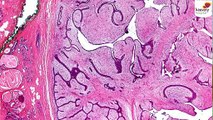

A brain tumor is a mass or growth of abnormal cells in your brain or close to your brain.

Brain Tumor Symptoms and Causes || Healthy Brain

What can be the primary causes and symptoms of Brain Tumor?